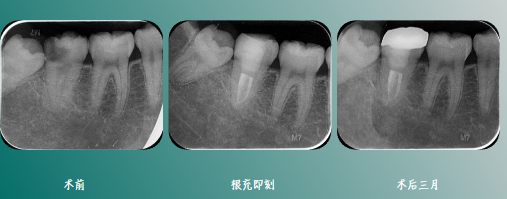

根充后髓腔内状态

影像学检查

一周复诊,无不适,叩(-),牙体预备,全冠修复。